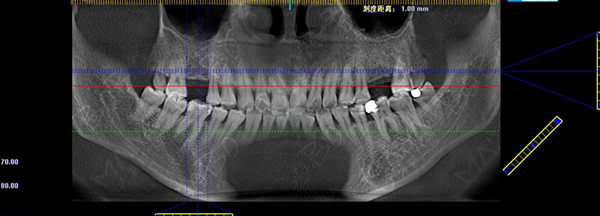

许女士术前口腔全景片

医生为许女士采取MAC数字化精确种植牙方案